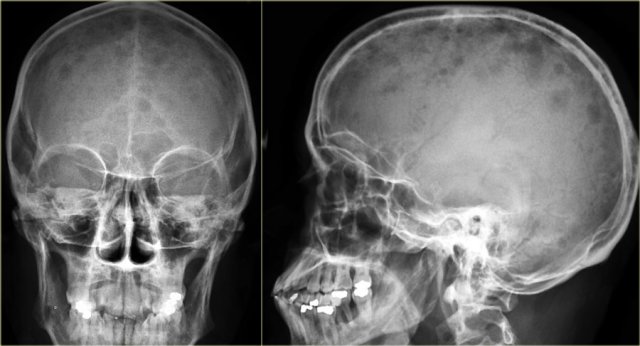

Multiple punched-out lesions in the skull.

This pattern is very characteristic fot multiple myeloma.

Also known as Swiss cheese-pattern.

Multiple small osteolytic lesions in a patient with multiple myeloma.